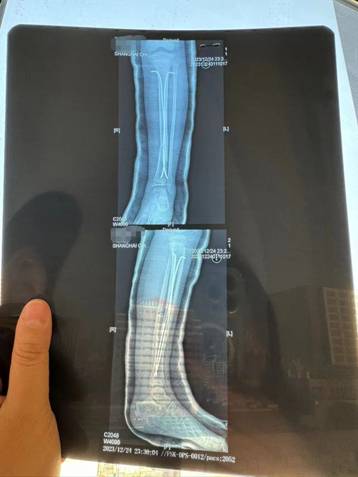

图说:乐乐左腿植入了两颗髓内钉,目前只能躺在床上。陈丽娜 摄

左腿植入了两颗髓内钉

目前只能躺在床上

乐乐被送到上海儿童医学中心后,门诊初步诊断为左腿胫骨骨折,并在当天做了6个小时的全麻手术,左腿里放置了两根髓内钉。

事发当日乐乐做了6小时全麻手术,左腿植入了两颗髓内钉。图源:受访者